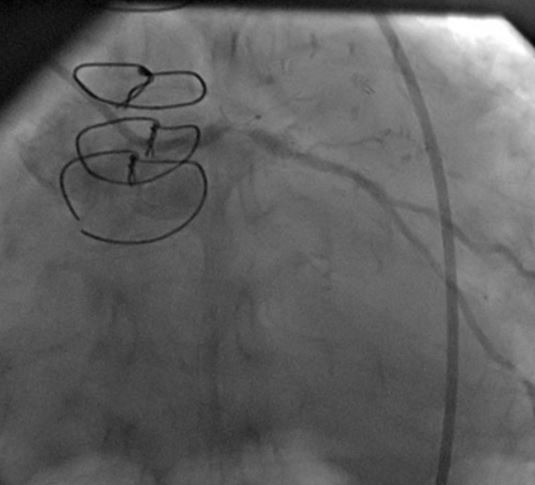

1) LM: subtotal ISR lesion (figure 2, figure 3)

A CLs guiding catheter was used to engage the left coronary artery, and a Choicd floppy guidewire passed through the lesion. The lesion was predilated with a 1.5x15mm and 2x10mm Maveric balloon (figure 4). Then a 3.5x18mm Xience v stent was deployed at 16atm (figure 5, figure 6, figure 7). Post-dilation was done with a 4x10mm Firestar NC balloon (figure 8). The final result showed TIMI-III flow with no residual stenosis (figure 9).